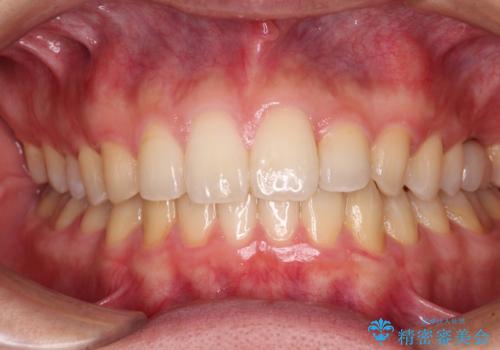

[ 矯正と補綴、総合歯科治療 ] クロスバイトを避ける前歯部審美ブリッジ

![[ 矯正と補綴、総合歯科治療 ] クロスバイトを避ける前歯部審美ブリッジの症例 治療後](https://seimitsushinbi.jp/wp/wp-content/uploads/2021/07/fcd77503a97e2f3a648f6e8698e34626-500x350.jpg?v=1626697051)